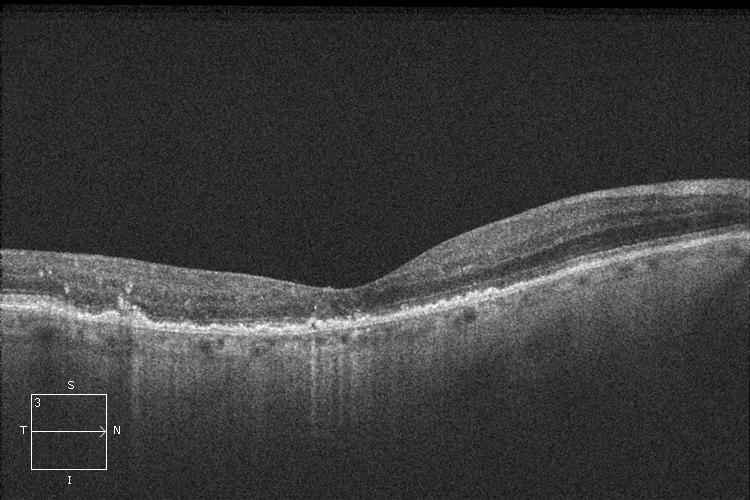

- La Degeneración Macular Asociada a la Edad (DMAE) húmeda o exudativa se diagnostica mediante la exploración del fondo del ojo bajo dilatación pupilar, la realización de una tomografía de coherencia óptica (OCT) y una angiografía fluoresceínica (AGF). Las 3 pruebas son complementarias y permiten conocer mejor el grado de DMAE húmeda para un enfoque terapéutico adecuado.

OCT. DMAE húmeda o exudativa